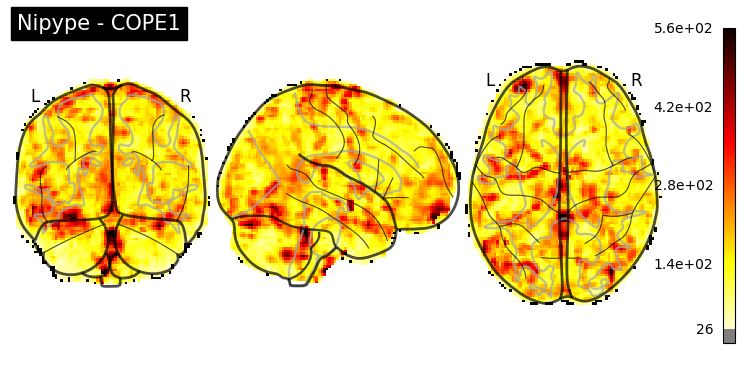

The first-level GLM#

Here we randomly choose the four copes from subject-09 run-1

nipype_cope1 = './output_level1/level1_results/09/results_dir/_subject_id_09/_level1estimate0/results/cope1.nii.gz'

nipype_cope2 = './output_level1/level1_results/09/results_dir/_subject_id_09/_level1estimate0/results/cope2.nii.gz'

nipype_cope3 = './output_level1/level1_results/09/results_dir/_subject_id_09/_level1estimate0/results/cope3.nii.gz'

nipype_cope4 = './output_level1/level1_results/09/results_dir/_subject_id_09/_level1estimate0/results/cope4.nii.gz'

plotting.plot_stat_map(nipype_cope1, bg_img=nipype_cope1, title = 'Nipype - COPE1', cmap = 'bwr', colorbar = False)

plt.show()

plotting.plot_stat_map(nipype_cope2, bg_img=nipype_cope1, title = 'Nipype - COPE2', cmap = 'bwr', colorbar = False)

plotting.plot_stat_map(nipype_cope3, bg_img=nipype_cope1, title = 'Nipype - COPE3', cmap = 'bwr', colorbar = False)

plotting.plot_stat_map(nipype_cope4, bg_img=nipype_cope1, title = 'Nipype - COPE4', cmap = 'bwr', colorbar = False)

../../_images/a7f7f387884673a96e62aa7d2d938a6b6487846759bc4500b6d0cff677c7358d.png ../../_images/bc743ce13891ebab23c9f6c7d4d668db8d11c9409d4f6e4580f7d63b35ecdb77.png ../../_images/228b3b22c00177a8ad5dc1793cbbc90dbfb495735196a4af47e73b899de0ca82.png ../../_images/babe8f68f0856f0f1608dfe550483d8ca862aae33a659d1f970a9fbe726f3bb1.png